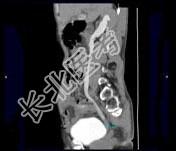

- 多项选择题男,53岁, 无痛性血尿2个月余,CT扫描如图示, 下列说法正确的是 ( )

A、右侧输尿管下段可见沿输尿管走行的软组织肿块影

B、软组织肿块边缘毛糙不平

C、其上方的输尿管扩张

D、考虑为输尿管移行细胞癌

E、考虑为输尿管内血块